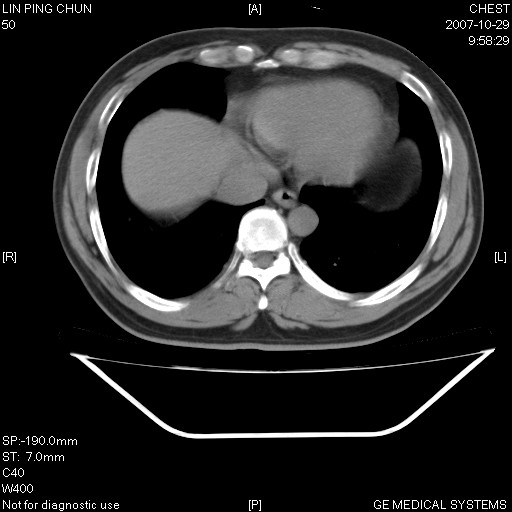

标题: CT10239:男,42Y.我自己的胸部CT扫描,今天10点突然咯血一次。

我自己胸部ct扫描,求助大家,我自己还不能给自己诊断。其他层面纵隔窗无异常。

补充:男,42y.今天10点突然咯血一次。余无异常。

谢谢大家!!!上传纵隔窗,请大家帮我分析。

上传纵隔窗看一看.